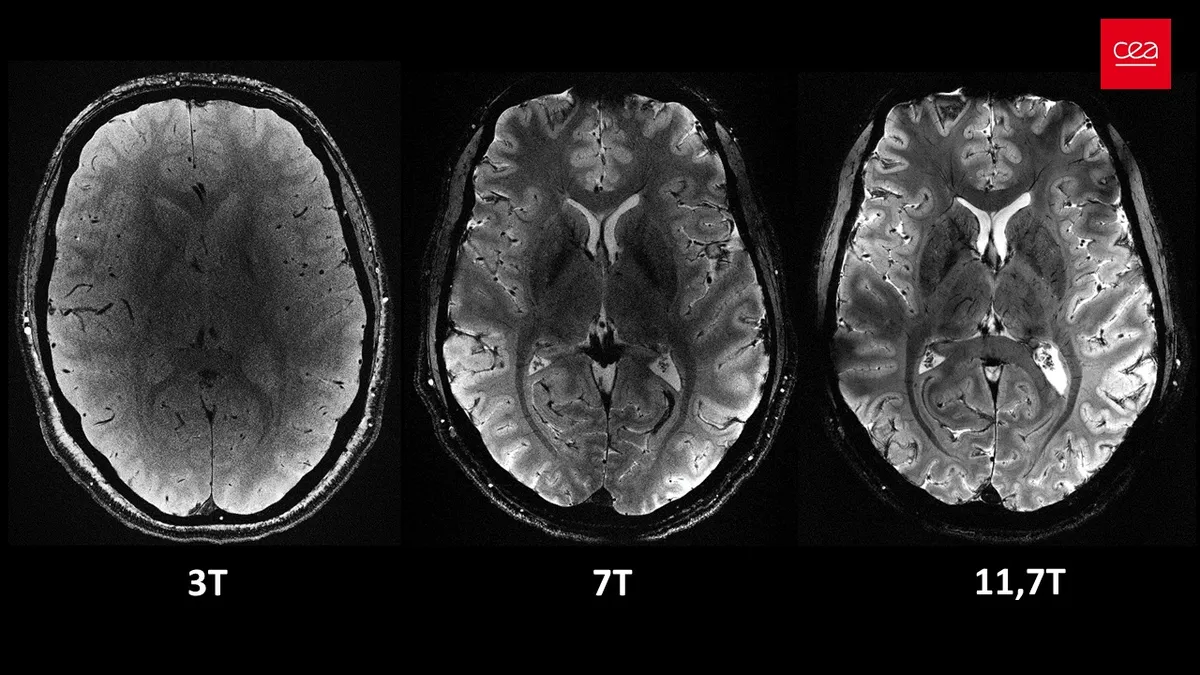

MR tarayıcıları, vücudu veya görüntülemek istediğiniz alanı güçlü bir manyetik alanla çevreleyerek çalışır. Tıbbi uygulamalarda yaygın olarak kullanılan cihazlar genellikle 1,5 veya 3 tesla (T) alan şiddetine ulaşabilir. Bir MR cihazının gücü arttıkça, elde edilen görüntülerin çözünürlüğü ve kalitesi de artar. Bu durum, vücutta “olmaması” gereken kitlelerin tespit edilmesini önemli ölçüde kolaylaştırır.

Şimdi ise, Iseult MR makinesi adı verilen yeni nesil bir cihaz, 11,7 T güce ulaşarak dikkatleri üzerine çekmektedir. Bu olağanüstü güç, yayınlanan beyin görüntülerinin kalitesini de gözler önüne sermektedir. Pratikte, bu yüksek çözünürlük, 1,5 veya 3T tarayıcıların alacağı görüntüleri çok daha kısa sürede elde edebilmek anlamına geliyor.